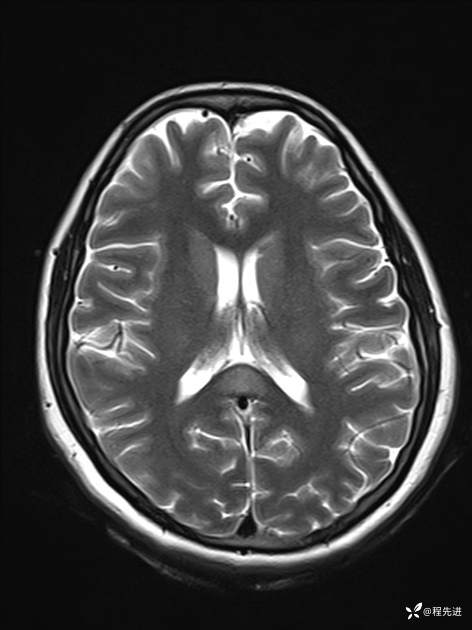

【患者信息】:女,25岁

【现病史及既往史】:言语含糊、意识状态改变1天。有下段剖宫产术10天病史。